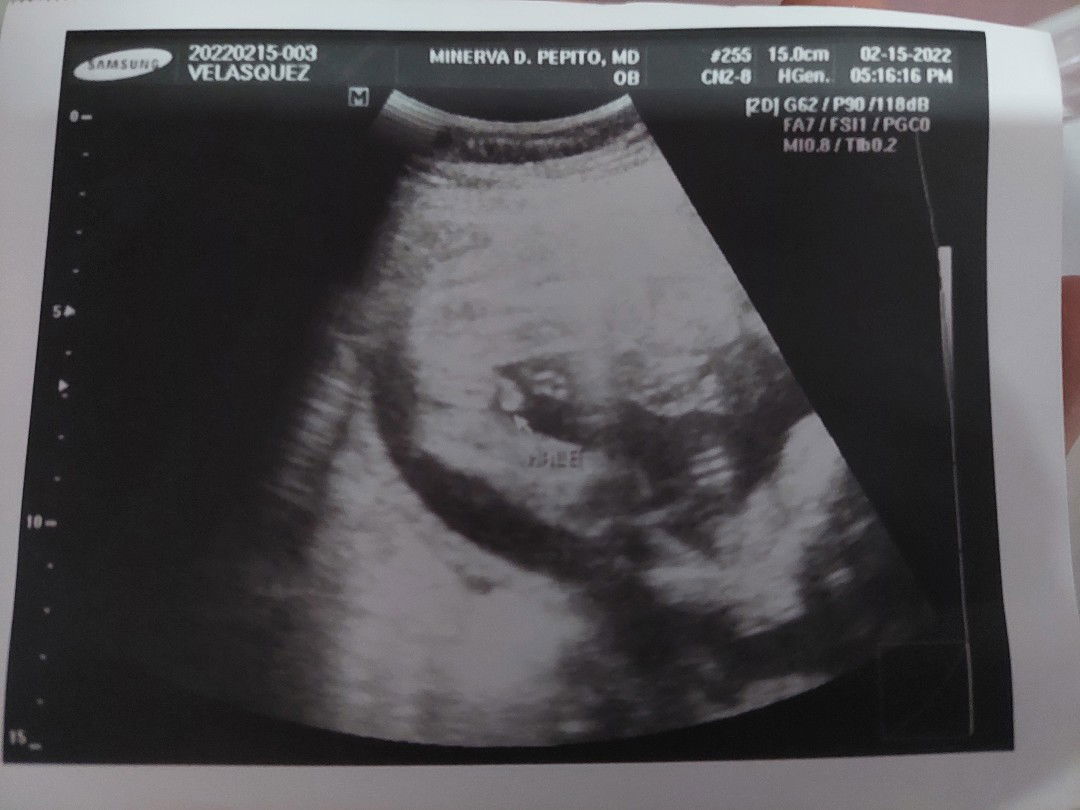

Diagnosis: IPUV 5 weeks 5 days

Hello mga mommy meron ba here na same diagnosis sakin? Tpos pinababalik ng 2 weeks, nabuo ba si baby ang ngka heart beat?